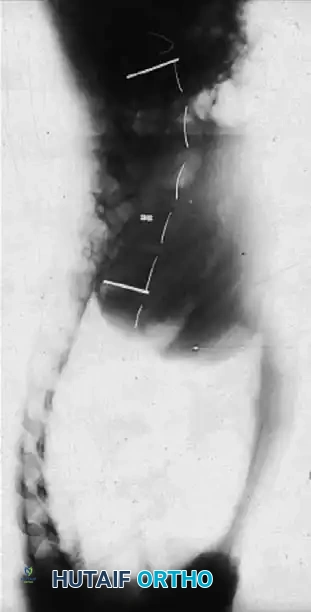

The biomechanical rationale for this procedure is rooted in the tension-band effect of the thoracic cage. In severe scoliosis, the ribs on the concave side of the curve become structurally contracted, acting as a rigid tether that resists coronal correction and derotation. Halsall et al. conducted pivotal cadaveric studies testing spinal flexibility before and after the sectioning of ribs on the tension (concave) side. Their findings demonstrated an average increase in coronal deflection of 53%, with the maximum increase in flexibility achieved when five or six apical ribs were resected or osteotomized.

Clinical Pearl: While concave osteotomies undeniably increase the flexibility of rigid curves, the advent of modern, high-density pedicle screw fixation systems has provided unprecedented three-dimensional corrective power. Consequently, the absolute necessity for concave rib osteotomies has diminished. However, in cases of severe, neglected, or exceptionally rigid deformities, it remains a highly effective adjunct. If performed, the prophylactic insertion of a chest tube is mandatory.